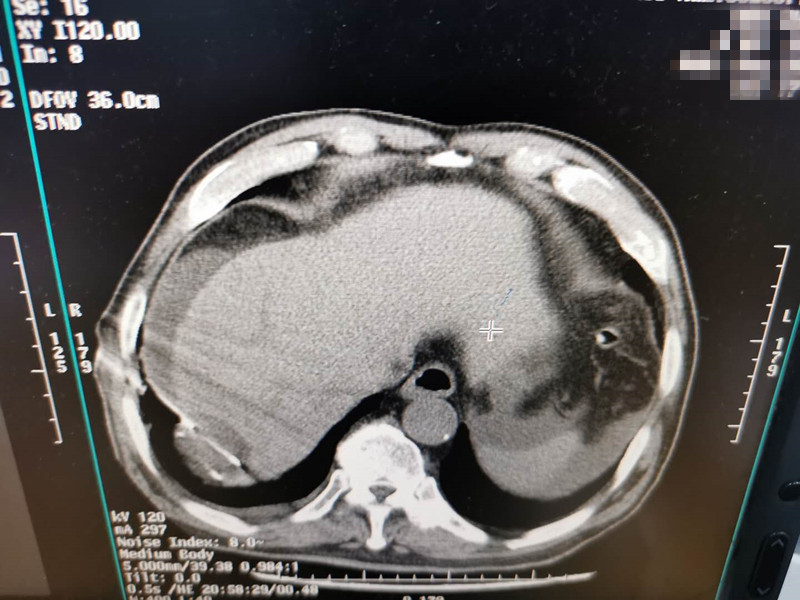

83岁肺部氩氦刀冷冻消融

发布人:美国氩氦刀技术官方网站    发布时间:2020/7/20 15:28:22